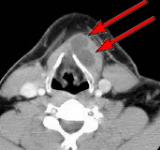

Fig.1 Fig.2 Fig.3 Fig.4

CLINICAL PRESENTATION: This patient presented with a mid-line and left paramidline mobile neck mass and was referred to AIC for a helical CT scan of the neck soft tissues.

HELICAL CT FINDINGS: The CT scan was performed on AIC’s Multi-slice, Multi-detector Helical CT Scanner with 2.7 mm axial sections at 2.5 mm intervals before and during infusion of low-osmolar, non-ionic contrast using a power injector. It shows a lobulated cystic mass (arrows) in the neck at and below the hyoid bone in the midline and to the left of it, with portions of it behind the hyoid bone and portions embedded in the left strap muscle.